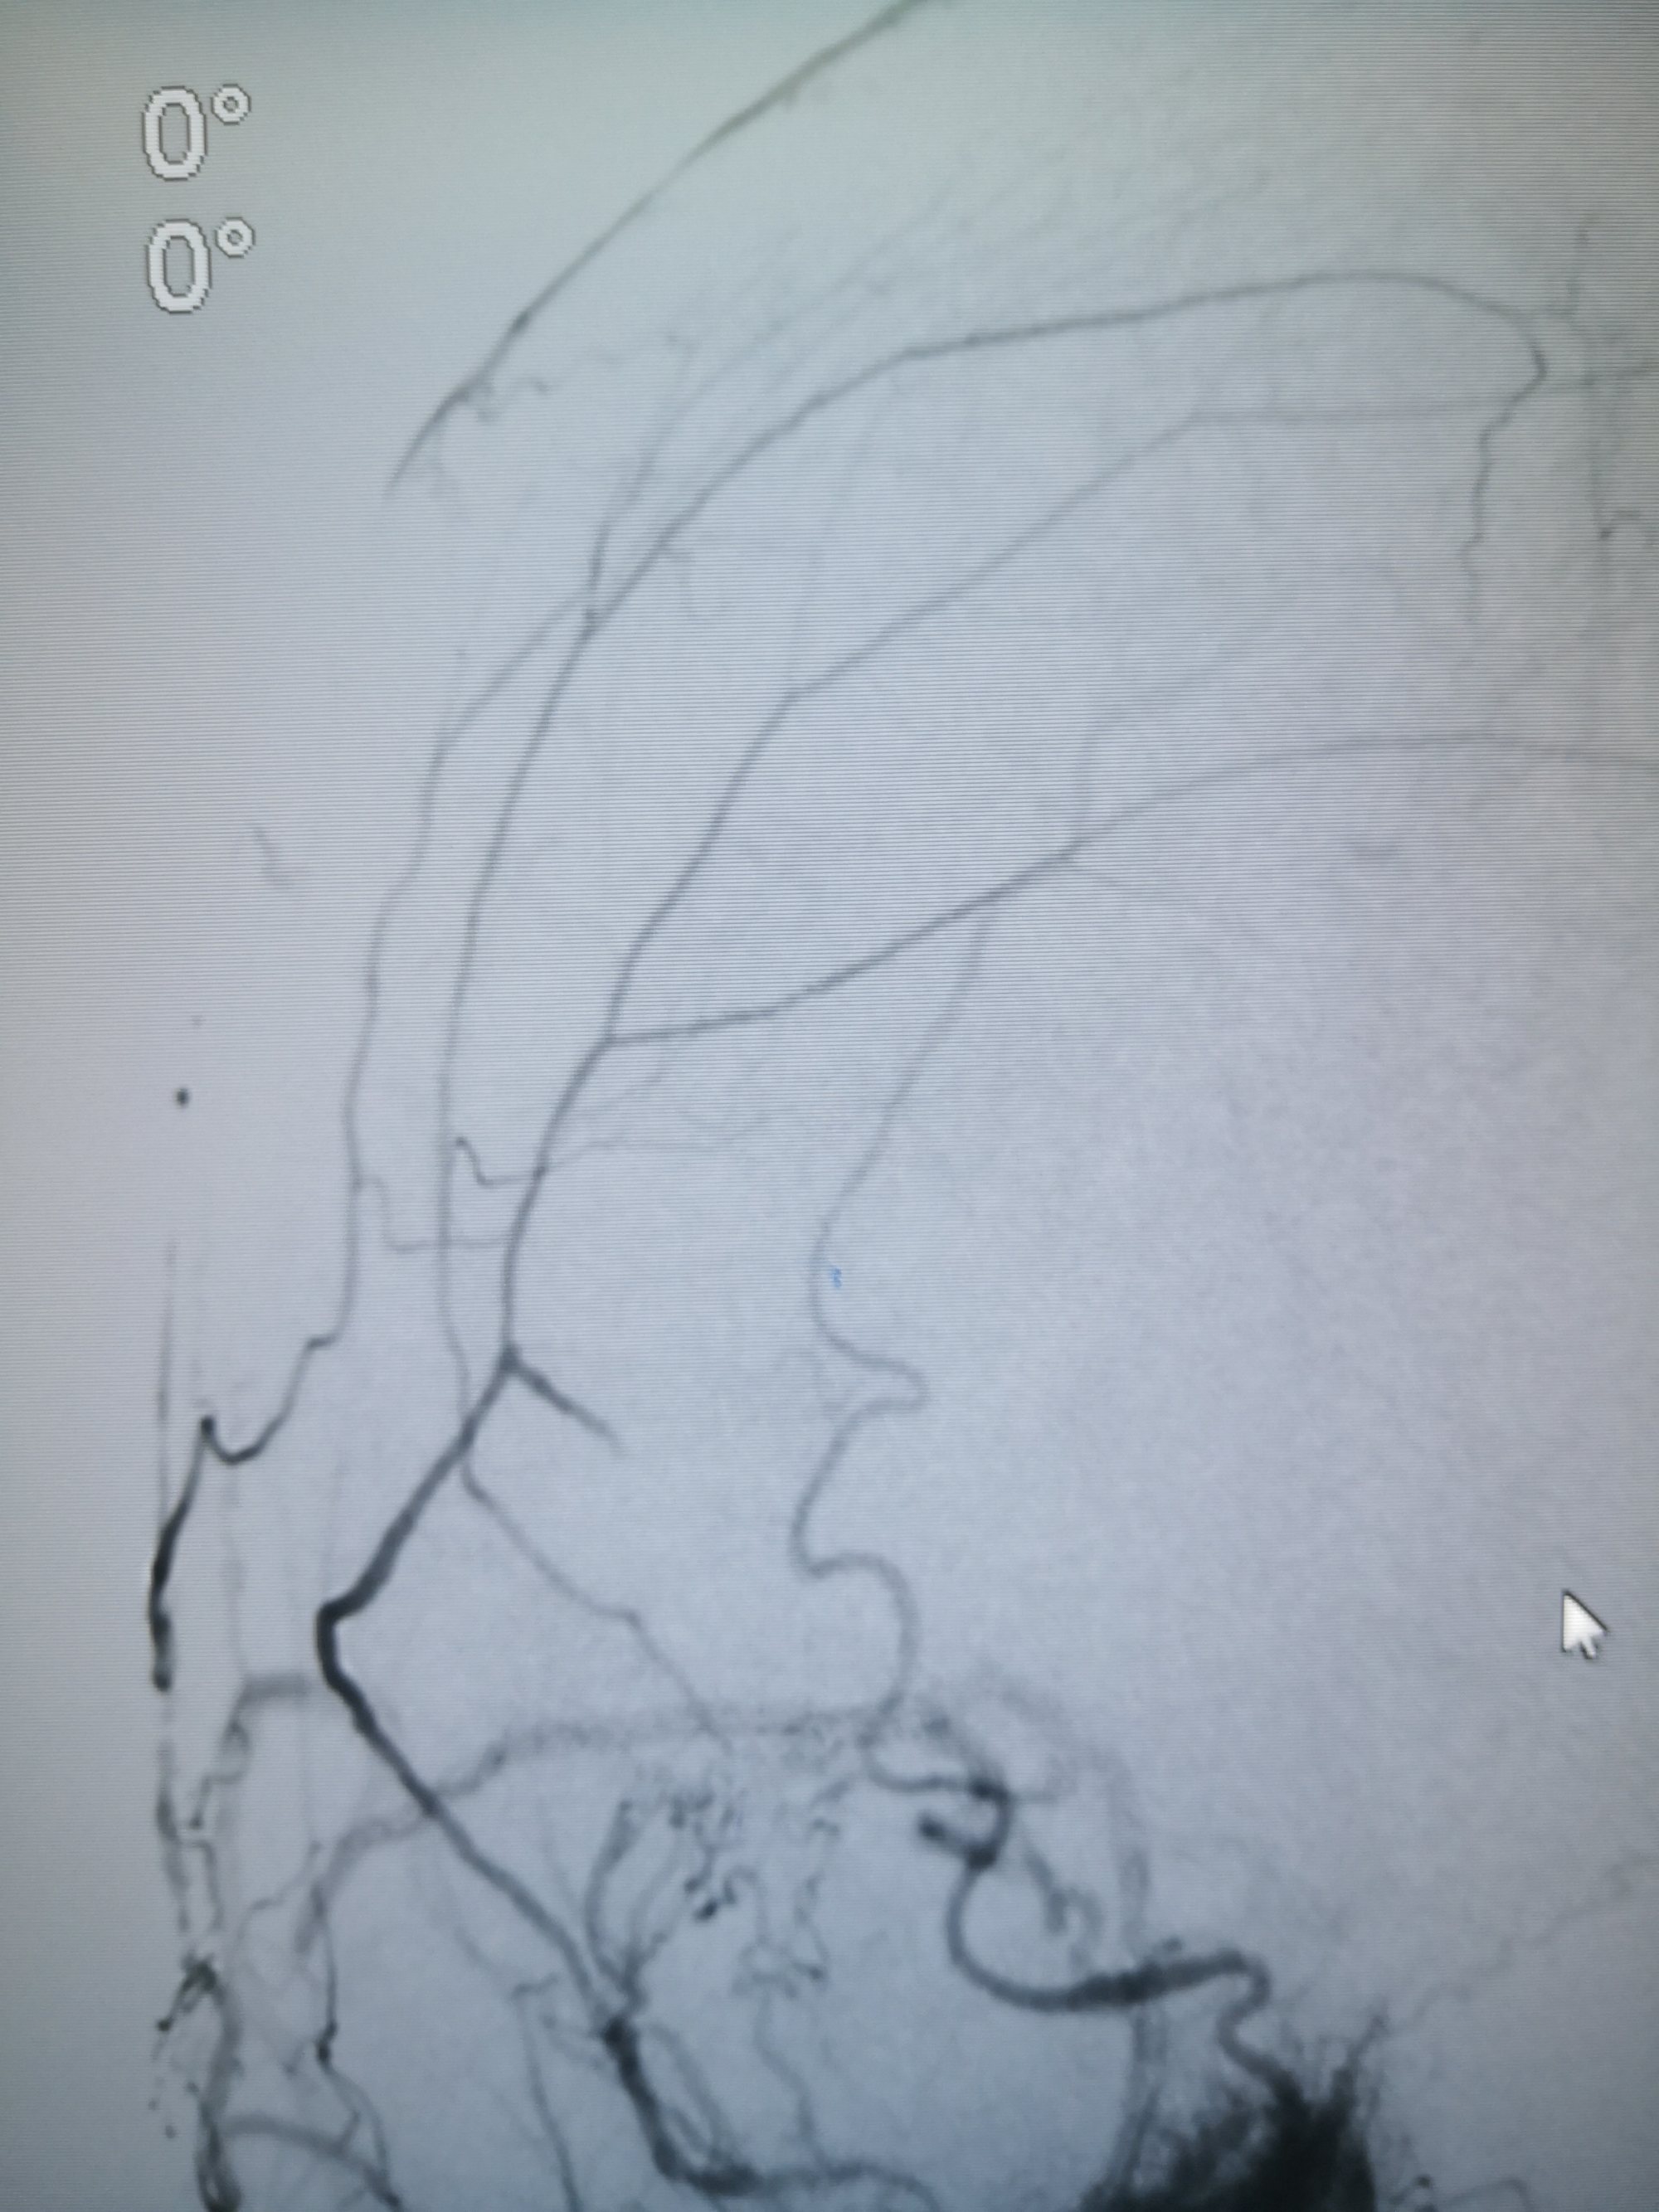

看看术前造影,迂曲的静脉,上矢状窦后三分之一及横窦已经不显影了

看看术前造影,迂曲的静脉,上矢状窦后三分之一及横窦已经不显影了